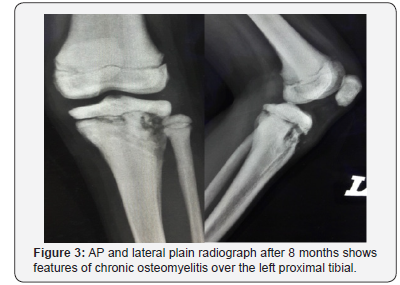

Ms A, an eight- year old girl met in a road traffic accident (motorcycle versus car). She was the pillion rider on a motorcycle rode by her sister. While making a U-turn, the front of their motorcycle was hit by a car at the speed of 30-40kmPH causing them to lose control of the motorcycle and she fell sideways landing on her left knee. There was no direct impact to her. She presented to the emergency department with complain of left knee pain, swelling and inability to weight bare. She was diagnosed with closed left tibial plateau fracture salter Harris type two and proximal third fibula fracture (Figure 1). She underwent closed reduction and percutaneous K-wiring of her left proximal tibia (Figure 2) which subsequently was complicated with osteomyelitis (Figure 3). On retrospective review of her initial plain radiograph, it was noticed to show generalized increase in bone density.

Due to the complication (osteomyelitis) of the initial surgery. She had to undergo wound debridement, and sequestrectomy a total of three times and treated with intravenous antibiotics for six weeks and continued with oral antibiotics for another six weeks. Total duration of admission to ward was seven weeks. She was followed up at two weeks upon discharge, the wound was healing well with healthy granulation, no discharge. She was unable to fully extend her left knee (flexion deformity of ten degrees), to which she was subjected for aggressive physiotherapy. At six weeks post discharge, the wound closed up, no more sinus or discharge and the flexion deformity improved to six degrees. She however still complains of pain over her leftproximal tibia on weight bearing and ambulation. Despite the adequacy of surgical and antibiotic therapy, at three months, six months and one year follow up she still experience pain over her left proximal tibia, significant enough to affect her daily activity (she refuses to walk, run and stand for long period). Pain is described as dull aching constant pain localized to the proximal tibia, no joint line tenderness. She also suffered permanent fixed flexion deformity of her left knee of six degrees.